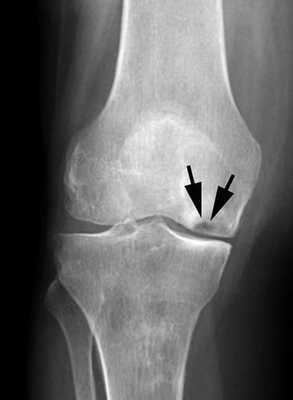

На снимке можно увидеть признаки асептического некроза внутреннего мыщелка бедренной кости.

Постепенно, с развитием заболевания может наблюдаться сужение суставной щели, сопряженное с травмированием хрящевой ткани сустава.